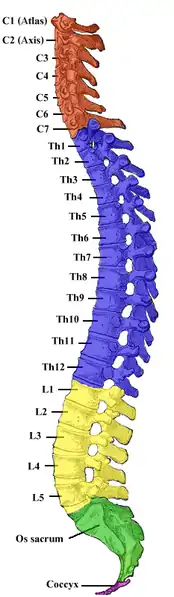

Spinal cord

The spinal cord is divided into 31 segments, located between the vertebrae. Each segment is defined by a posterior root entering it and an anterior root exiting it. Each of these roots is the end of a spinal nerve connecting the spinal cord to the body. The vertebral column is divided into four groups of vertebrae: (from top to bottom) cervical, thoracic, lumbar, and sacral.[4]

The lateral grey column is present at 17 levels of the spinal cord, specifically through levels T1-L2 (sympathetic outflow) as well as through levels S2-S4 (parasympathetic outflow).[5] Both these segments are located within the first thoracic vertebra to the first or second lumbar vertebra as the spinal cord ends here and the nerves form the cauda equina.